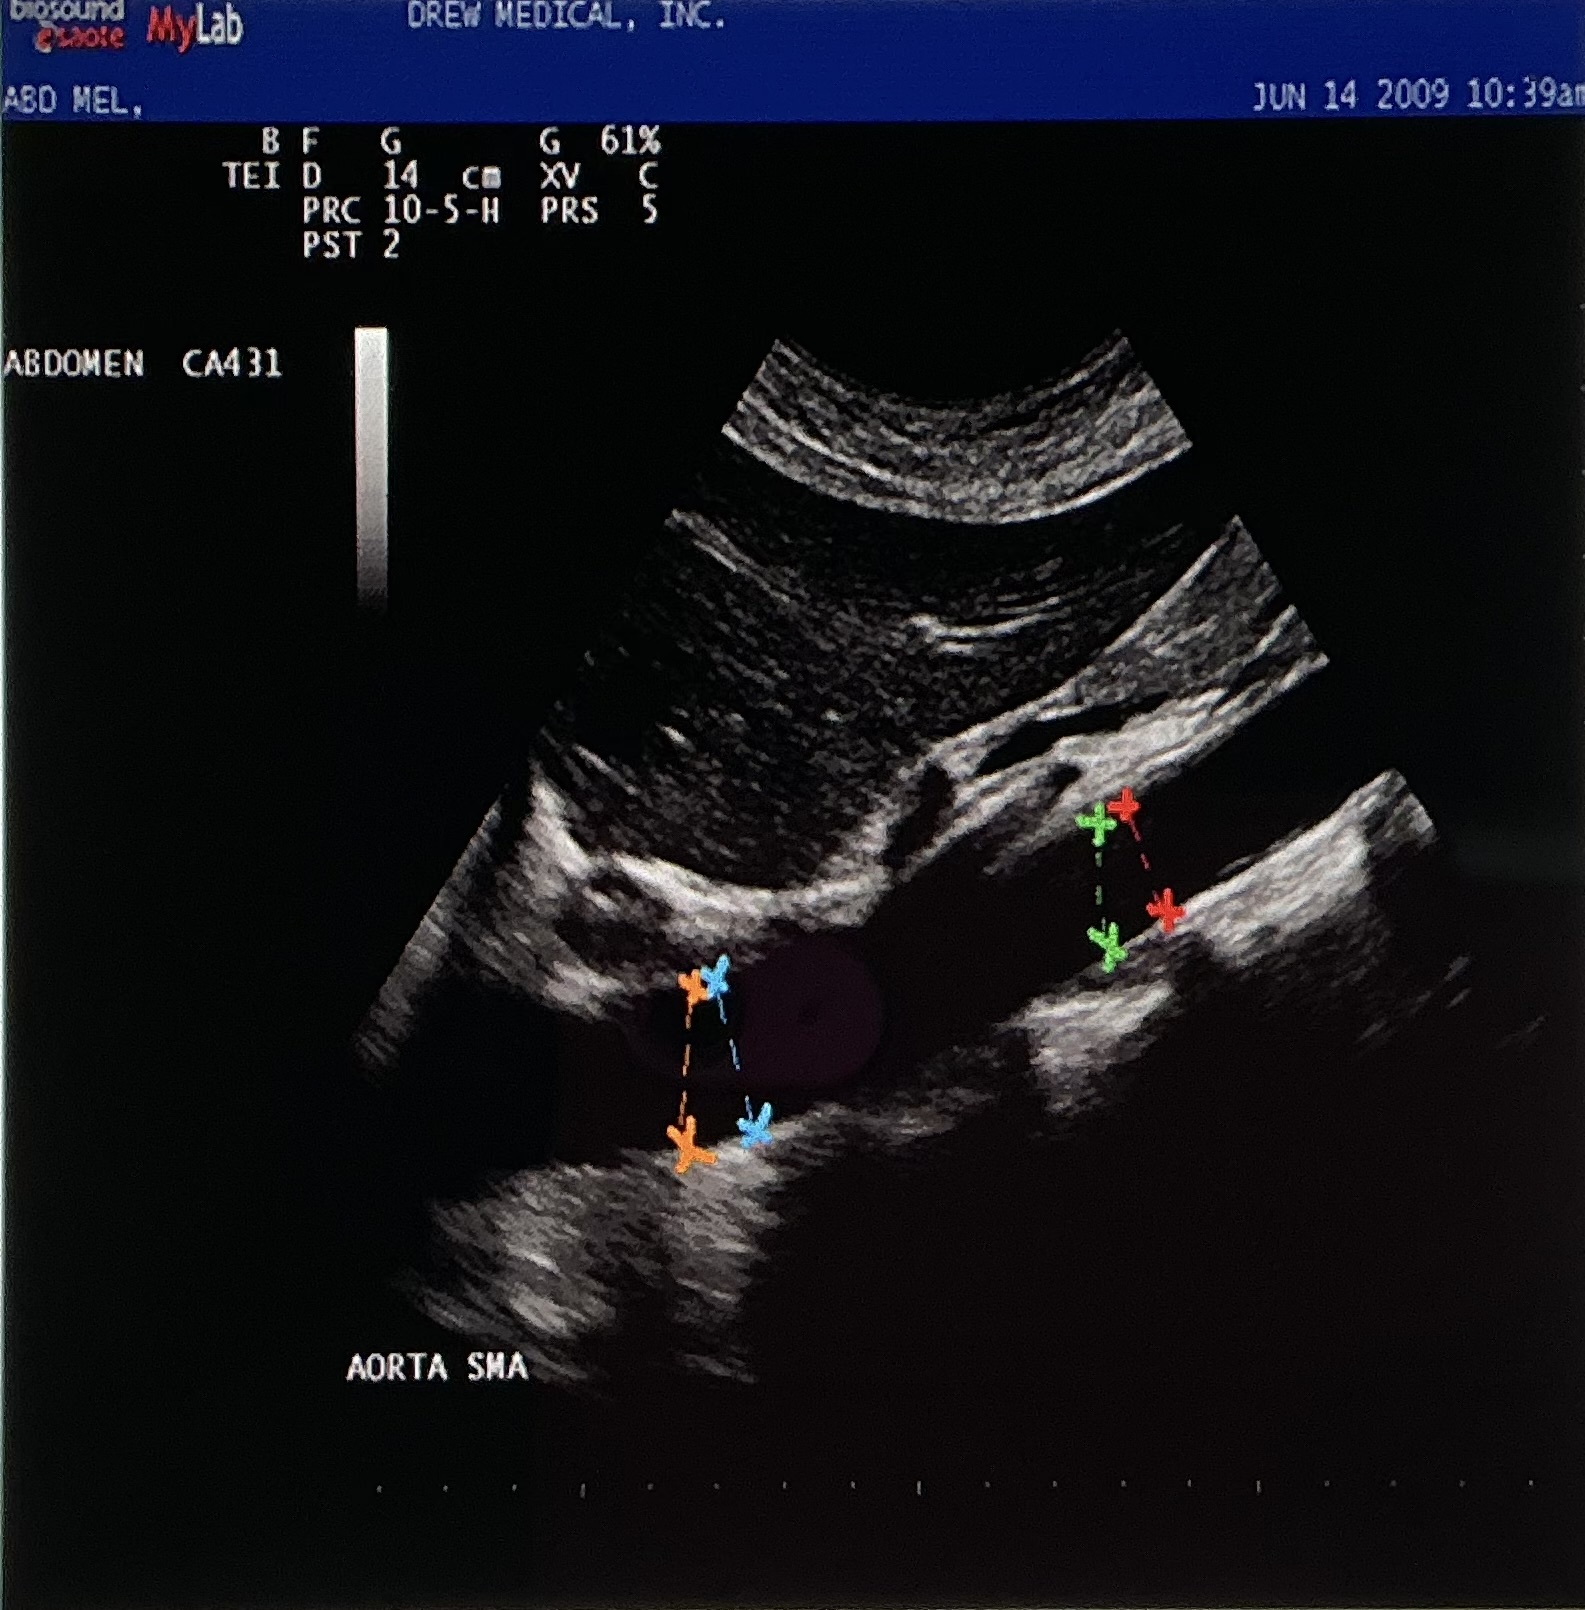

Which of the following colors of cursors are demonstrating a CORRECT AP measurement of the mid aorta segment on the image?

red

What vascular landmark divides the aorta into proximal and mid segments?

SMA

The image is demonstrating the aorta from what probe orientation?

longitudinal